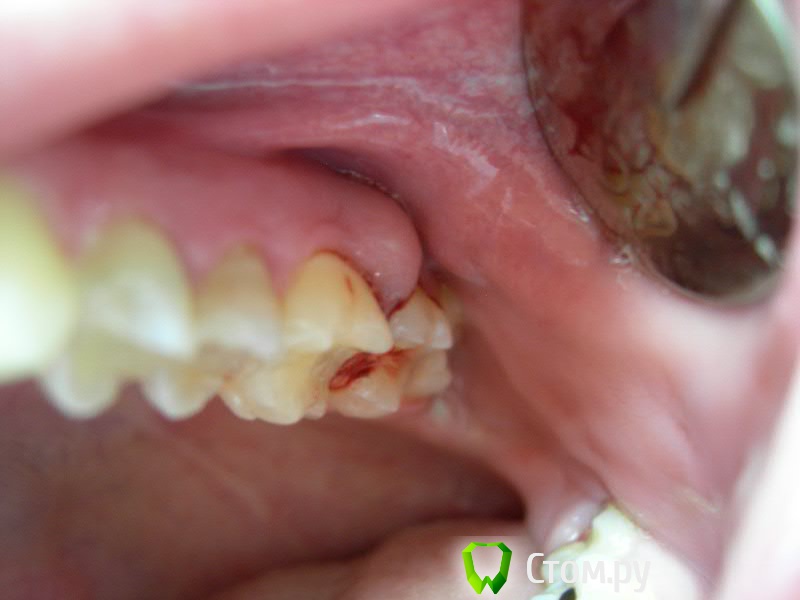

cor Опубликовано 22 декабря, 2013 Поделиться Опубликовано 22 декабря, 2013 Я тут на форуме недавно совсем, но заметил тему как пациент спрашивал про матрицу, что больно и неудобно ему было. Дак вот, что бывает, если её не поставить. Обычная поликлиника, извиняюсь за качество снимков) (_дело было в 2012 году_)Пациент Е. (молодой 1987г.р.) обратился с жалобой на "надутыш на десне" в области 2.6, 2.7 зубов. (далее с моих слов) Месяц назад лечил причинные зубы по поводу не осложненного кариеса На вестибулярной поверхности десны в проэкции межзубного промежутка 2.6 и 2.7 абсцесс. Сделали снимки - всё хорошо с периодонтом.Фото в полости рта . На этих зубах (и заодно на десне) лежала одна общая пломба (II класс по Блэку). При зондировании абсцесс был вскрыт. Промыл хлоргексидином 0,1%, закрыл бОльшую полость (26 зуб) дентин пастой, 2.7 - просто остался вообще без пломбы... полость маленькая, не подготовленная, десна жутко кровит, чего зуб крошить по чем зря? (пломбировать было не возможно). Между зубов что то болталось - думал пломбу в пришейке не снял... Достал некротизированную межзубную перегородку . Назначил через день - воспаление стихло, почти не кровило - нить поставил, матрицу поставил, и вуаля!) Сначала восстановил 2.7. Потом 2.6, с матрицой, естественно. Ну и своим Filtek ом.Вчера случайно увидел у коллеги на приёме, всё как после лечения - , а прошло полтора года. Так что доктора, особенно начинающие, особенно в ГОСе, не пренебрегайте матрицами. Ну и удачи в пломбировании 2 класса без новых примочек И делитесь опытом с такими же, как я, не опытными, буду благодарен! 12 Ссылка на комментарий